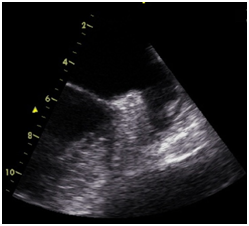

The most notable association between the LAA and disease is in the context of AF. In this setting, reduced contractility and stasis of the LAA occur, resulting in thrombus formation and thereafter the potentially catastrophic consequences of embolisation. In individuals with non-valvular AF, 90% of thrombi have been identified within the LAA; (Figure 1).14 Additionally it has been observed that up to 14% of patients have thrombus identifiable in the LAA within 3days of AF onset.15 It is these observations which have led to the LAA being termed ‘our most lethal human attachment.16 Remodelling of the LAA in subjects with AF has been observed with chamber enlargement and decreased pectinate muscle volume.17 Typical histological appearances include endocardial thickening, fibrosis and myocyte hypertrophy.18 A reduced LAA peak flow velocity studied during transoesophageal echocardiography (TOE) is established to be an independent and powerful predictor of thromboembolic risk.19 Likewise LAA morphology has been proposed as another marker of thromboembolism with the ‘cauliflower’ LAA conferring the highest risk of thrombus. In contrast patients with a ‘chicken-wing’ appearance LAA have lowest risk of embolism.7 Similar to the LA, the LAA has been shown to increase in size in patients with a history of hypertension when compared with controls. This was also associated with a reduction in emptying velocities as demonstrated during TOE.20 Likewise it appears that the LAA also plays a dynamic role in the setting of left ventricular dysfunction. Firstly left ventricular impairment results in a 10-fold increase in LAA ANP concentration.10 Furthermore, another study indicated that after successful heart failure therapy, LAA function improved significantly. It was also noted that, after treatment, LAA size reduced markedly more than LA size, demonstrating relatively increased compliance.21

Figure 1 Thrombus identified with in the left a trial appendage during TOE.